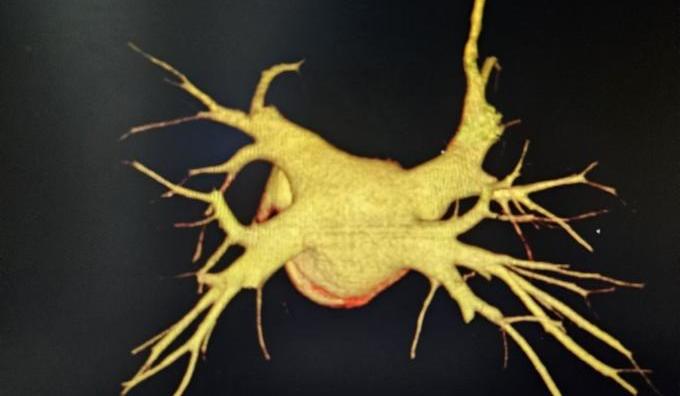

周某,78岁,长期受到持续性房颤的困扰,合并冠心病、高血压,并有一次卒中史,病程长达十余年。起初,症状表现为偶发的心悸和胸闷,但近几年症状逐渐加重,发展为频繁气短、乏力,严重影响了日常生活。考虑到他的卒中史以及房颤带来的潜在风险,且曾因心脏功能异常植入过起搏器,周爷爷的治疗方案在兰州大学第一医院心血管团队的精心制定下,采取了个性化的综合治疗方案,不仅通过先进的脉冲消融术精准处理房颤,还结合其卒中风险高的特点,施行了经皮左心耳封堵术,从源头预防卒中发生,为患者提供全方位保护。这一双管齐下的治疗策略,不仅显著改善了心律失常,还为患者的未来健康筑起了一道坚实的屏障。

FARAPULSE导管花瓣消融

左心耳封堵器完美封堵